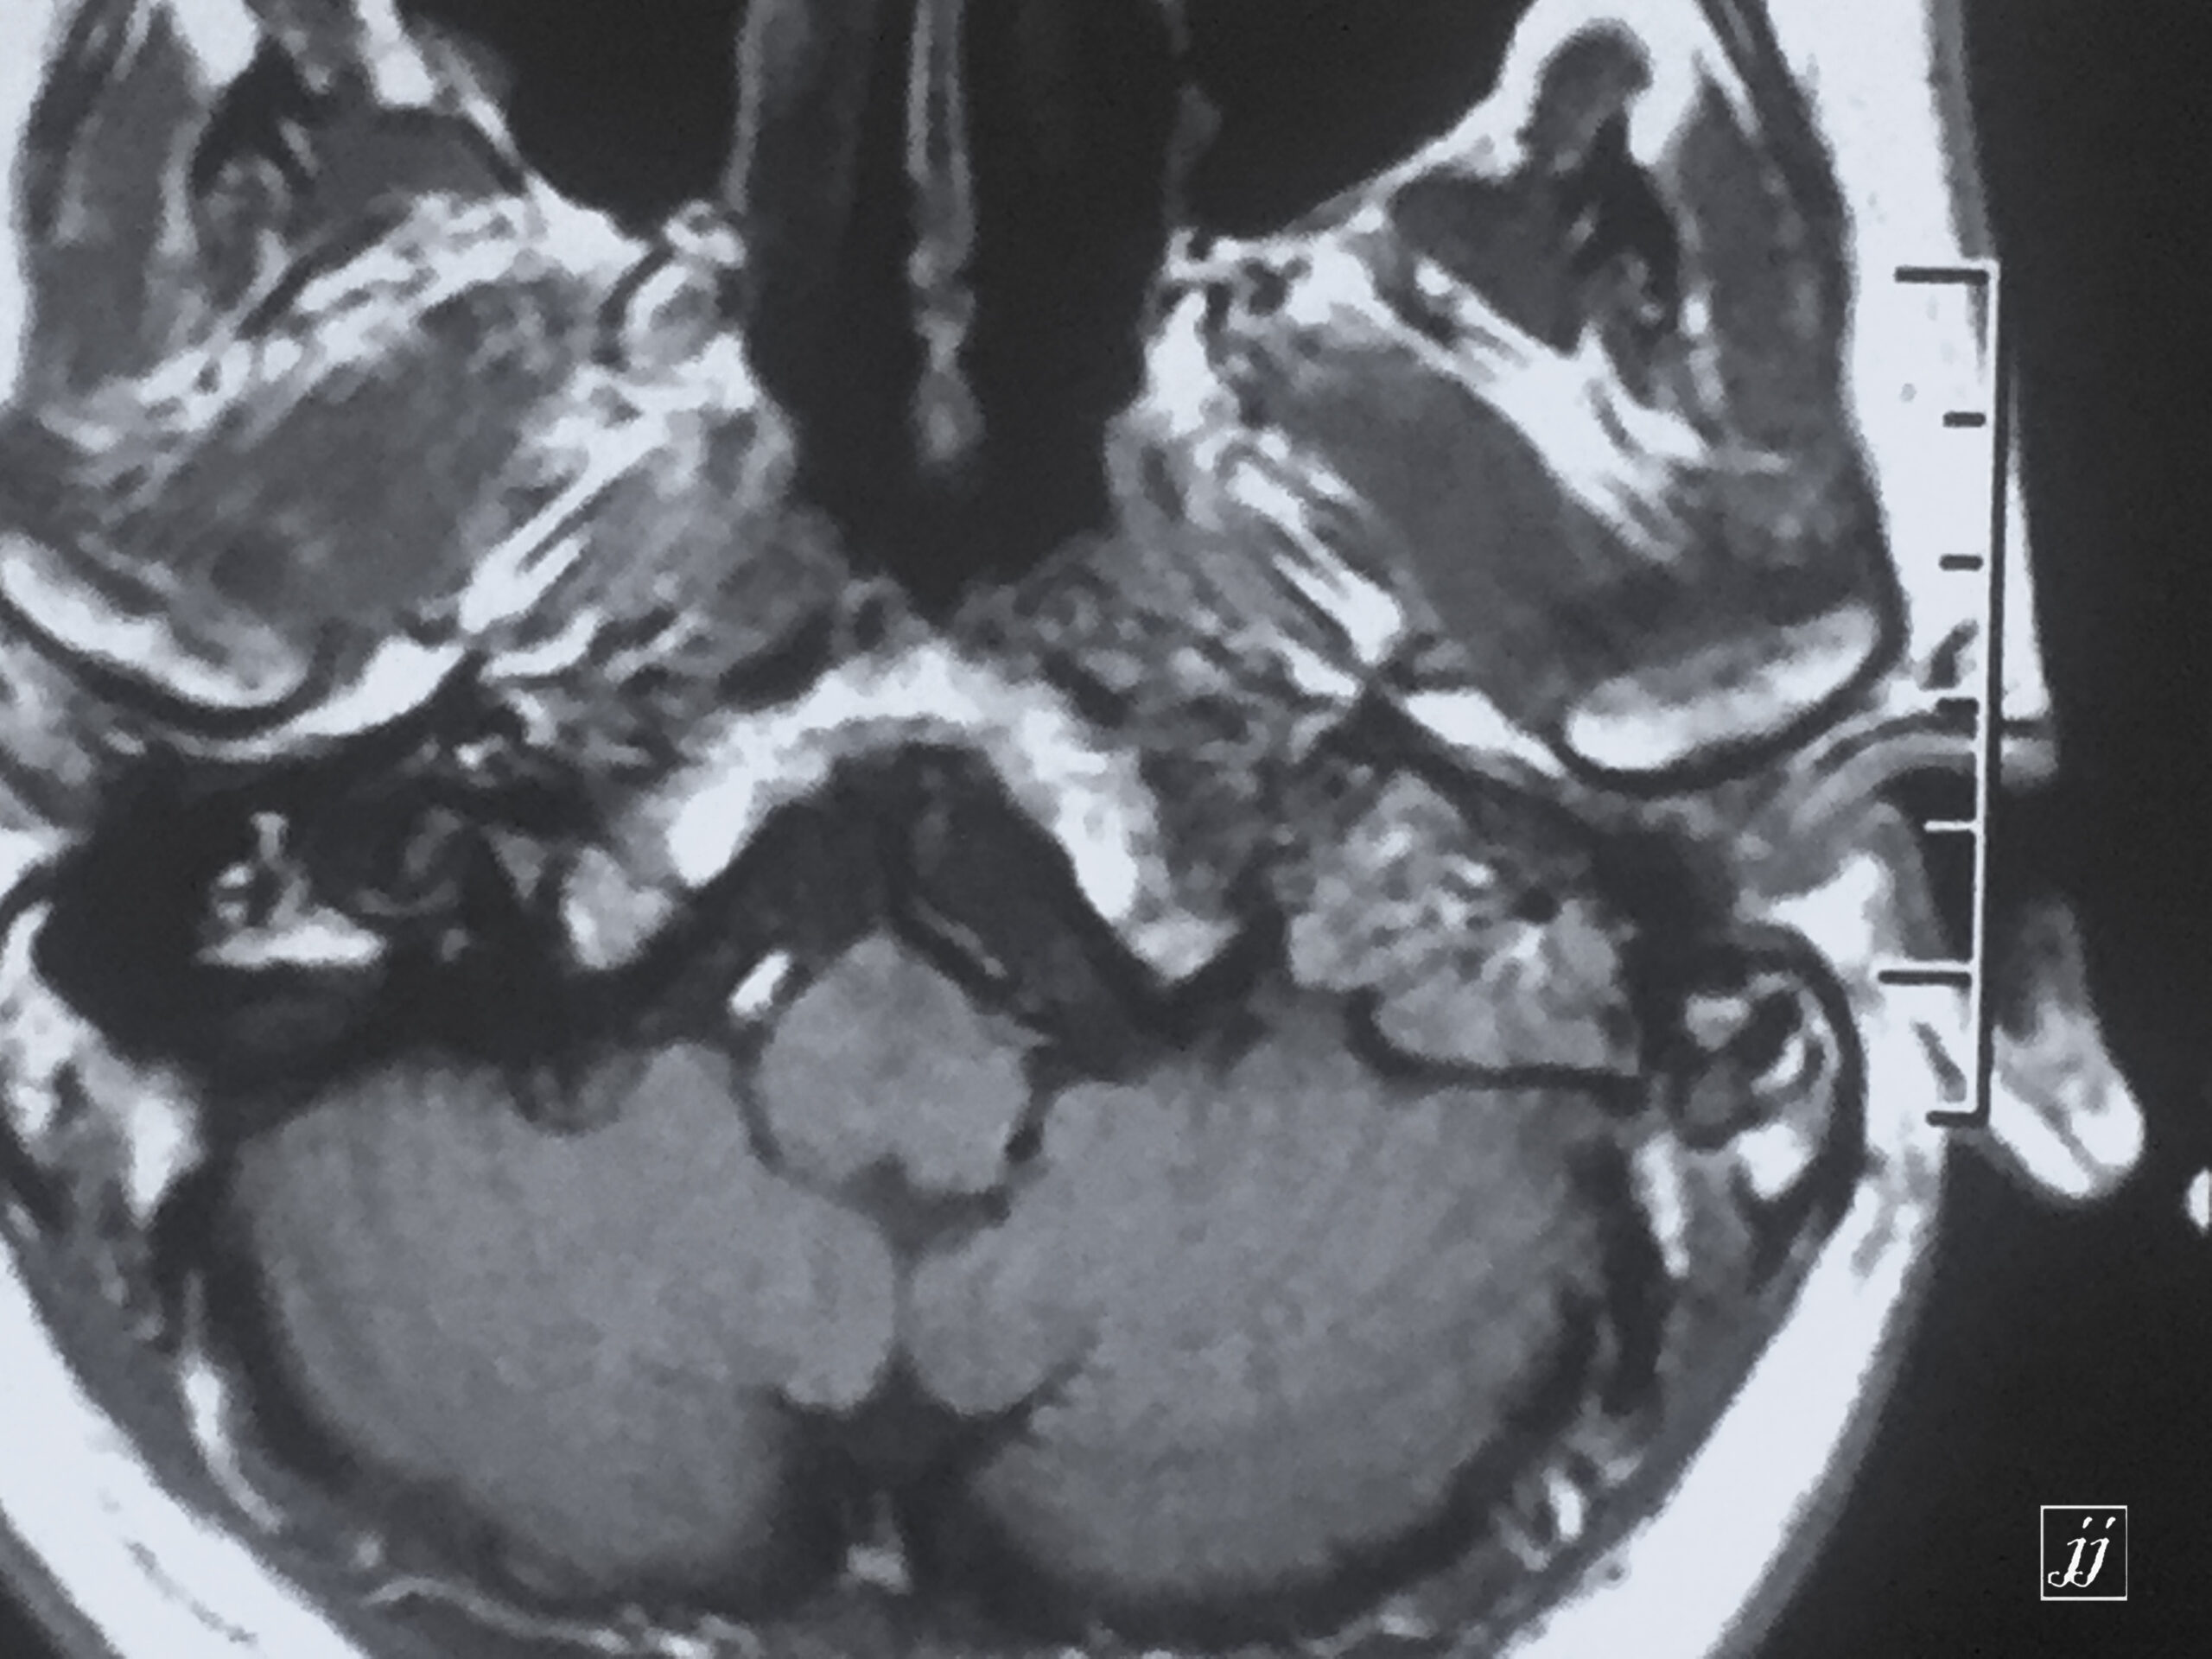

Brain- left glomus jugulars tumor (7)